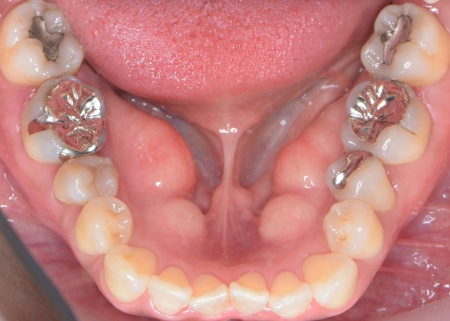

さらに、下顎の内側には下顎隆起(かがくりゅうき)という骨の出っ張りが見られました。

これは、強く噛む力が長期間かかることで骨が発達して発生するものなので、奥歯への過度な負担を示しています。

続いて噛み合わせを拝見したところ、前歯がしっかりと噛み合わない開咬(かいこう)という状態です。

この開咬により、本来前歯で分散して受け止めるべき噛む力が、すべて奥歯に集中していることがわかりました。そのため下顎隆起が発生し、また重度歯周病の大きな原因になっていると考えられます。

また、治療によって奥歯に過度な力がかかりにくくなったため、舌の動きをスムーズにしつつ歯磨きなどのセルフケアがしやすくなるよう、下顎隆起の除去を行いました。

下顎隆起を除去しました。